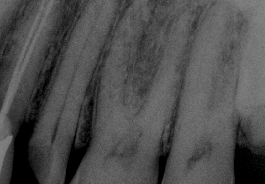

Bruxir Crown, Hairline Fracture, Prepared Canals, Postop Root Canal